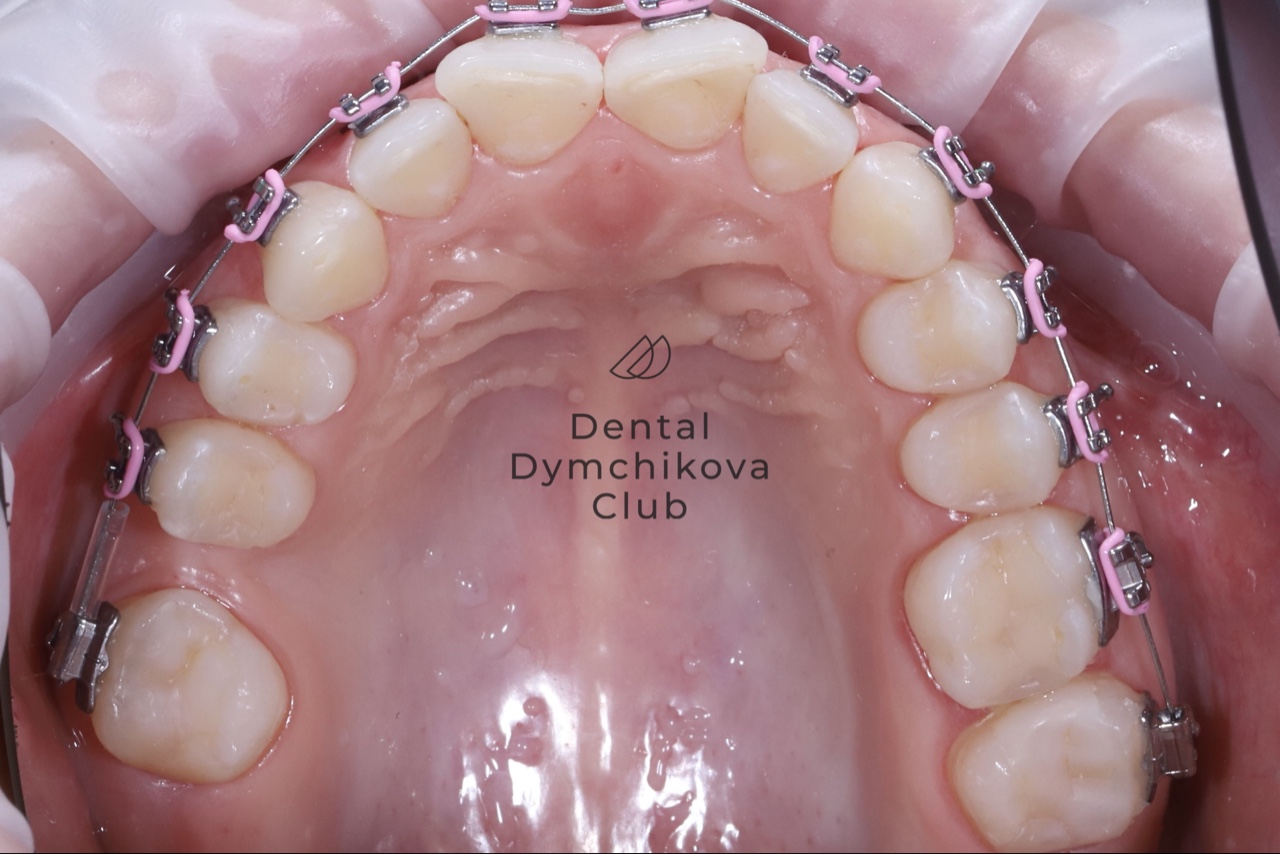

Ортодонтическое лечение, имплантация, протезирование (часть 1)

Пациентка, 34 года (часть 1).

Жалобы: на невозможность имплантации в области зуба 1.6, неровно расположенные нижние зубы, некомфортное положение нижней челюсти (хочется расслабить челюсть), щелчок в правом ВНЧС.

Лечение:

1) санация полости рта (лечение кариеса)

2) удаление 1.8, 2.8, 3.8, 4.8 и сверхкомплектный нижний резец

3) ортодонтическое лечение (брекеты, минивинты)

4) имплантация 1.6 на этапе ортодонтического лечения

На данный момент находится на лечении зубов и протезировании после снятия брекетов.

Срок лечения 2,5 года.

Доктора: Ефимова Дарья Юрьевна, Дымчикова Анна Вавиловна, Лебедева Адиса Тумэновна.

Ортодонтическое лечение, имплантация, протезирование (часть 2)

Пациентка, 34 года (часть 2) ВЕРХНЯЯ ЧЕЛЮСТЬ